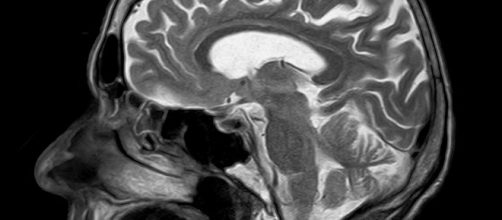

Magnetic resonance imaging (MRI) scans are painless, but for the patient waiting for the scan to reveal potential health issues, the emotional strain can be simply terrible. Many patients discuss their fears on Twitter.

Apart from the stress of knowing the scan might turn up some bad news, the MRI process involves confinement in a tight space. On top of this, the patient may not move or fidget. Of course, this is immediately what the body wants to do. Angela said, “Every muscle feels as though it just has to explode with energy...Now!” The noise of the machine is alien to us and the outcomes of the scan, while fascinating in their detail, can be very bad news.